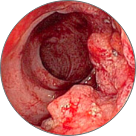

Tromboza proširenih vena anusa sa lokalnom nekrozom tkiva

Venska zapušenja s patološki izmenjenim varikoznim venama

Submukozno krvarenje koje dovodi do nekroze tkiva i anemije

Rak rektuma

Hemoroidi su ozbiljna bolest koja pogađa jednu od dve osobe širom sveta. Bol, peckanje, svrbež i krvarenje početni su simptomi koje ni u kojem slučaju ne treba zanemariti. Kao rezultat ulaska krvi u venski pleksus rektuma, dolazi do upalnog stanja, nakon čega se na rektalnom tkivu stvaraju krvavi čvorovi.